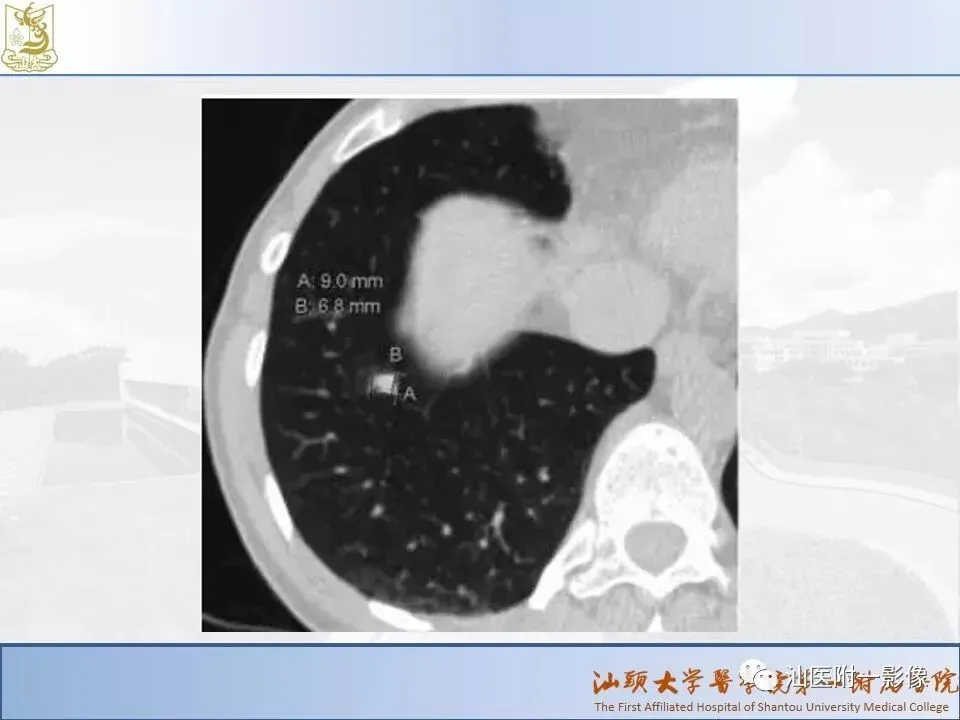

肺结节分类、处理及浅识肺结节分类影像报告和数据系统(Lung-RADS)

来源:汕医附一影像

说明:本课程病例主要来源于本院病例及参考资料,

无涉及病人隐私,仅做教学用途。